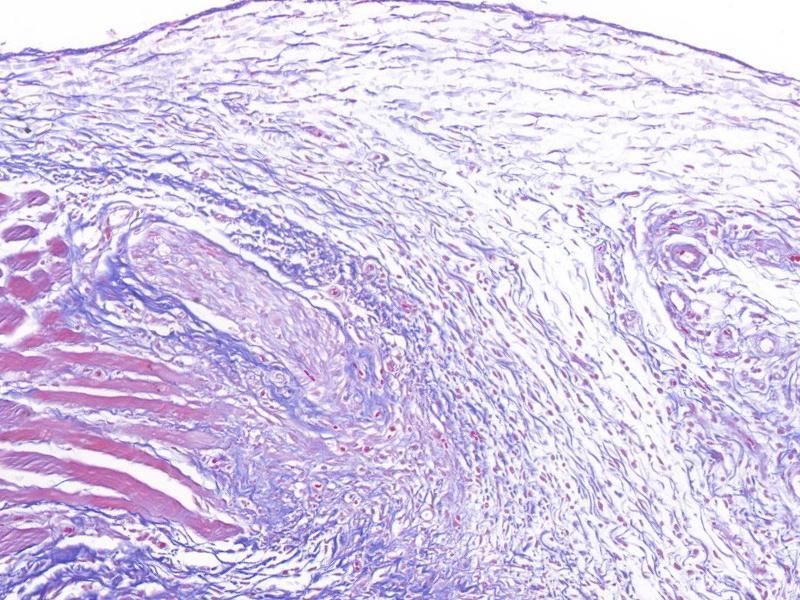

masson染色

编号:YSY10115

天狼星红染色

编号:YSY10120

EVG染色

编号:YSY10126